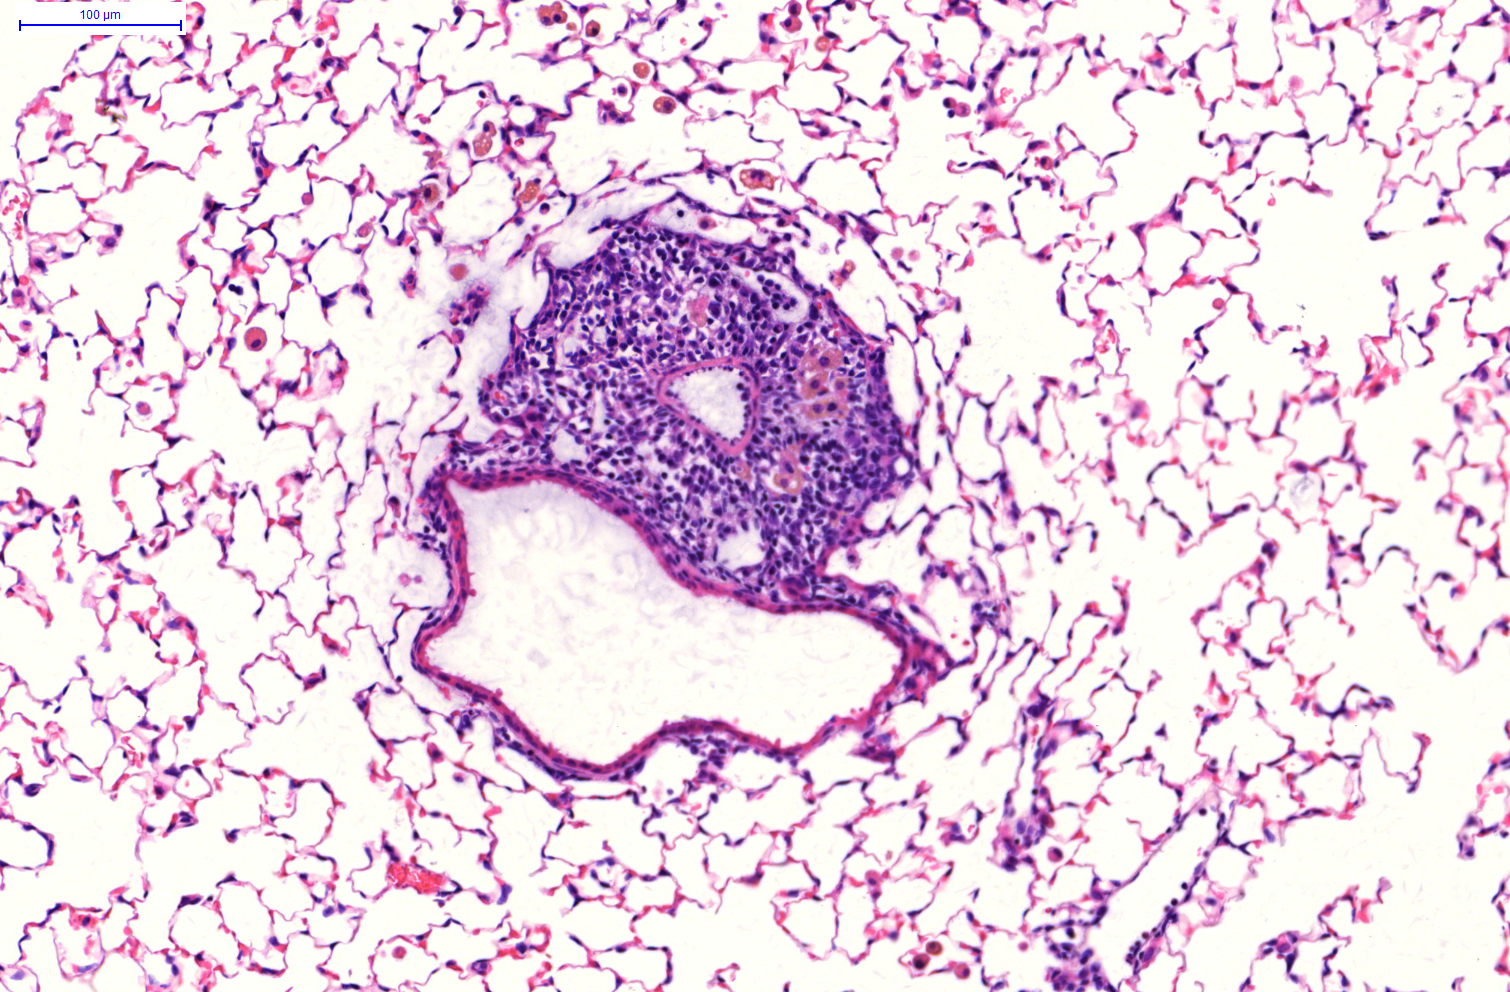

In der aktuellen Arbeit konnte ein Team um Dr. Ali Önder Yildirim nun den Entzündungsprozess näher aufklären. „Wir haben uns dabei auf tertiäre Lymphknoten* in den Bronchien konzentriert“, erklärt Yildirim, kommissarischer Leiter des Instituts für Lungenbiologie am Helmholtz Zentrum München, Mitglied im Deutschen Zentrum für Lungenforschung (DZL). Konkret untersuchten die Forscher die sogenannten induzierbaren Bronchien assoziierten Lymphknoten, kurz iBALT. „Mittlerweile geht man davon aus, dass die Entstehung von iBALT ein ganz zentraler Aspekt bei einer Verschlechterung von COPD ist – wie er aber entsteht war bis dato unklar“, so der Studienleiter weiter.

„Wir wollten nun herausfinden, ob das auch im Umfeld der Lunge und speziell bei einer durch Zigarettenrauch bedingten COPD so ist“, berichtet Yildirim. Tatsächlich fanden die Forscher sowohl im Versuchsmodell als auch in der Lunge von COPD-Patienten erhöhte Mengen der Enzyme, die für den Oxysterol-Stoffwechsel verantwortlich sind, begleitet von ins Gewebe einwandernden Immunzellen. Weitere Versuchsreihen zeigten zudem, dass die iBALT-Bildung gehemmt ist, wenn die Stoffwechsel-Enzyme nicht vorhanden sind. Dadurch wurde auch das Einwandern von Immunzellen verhindert und die Lunge nahm trotz Zigarettenrauch keinen Schaden.